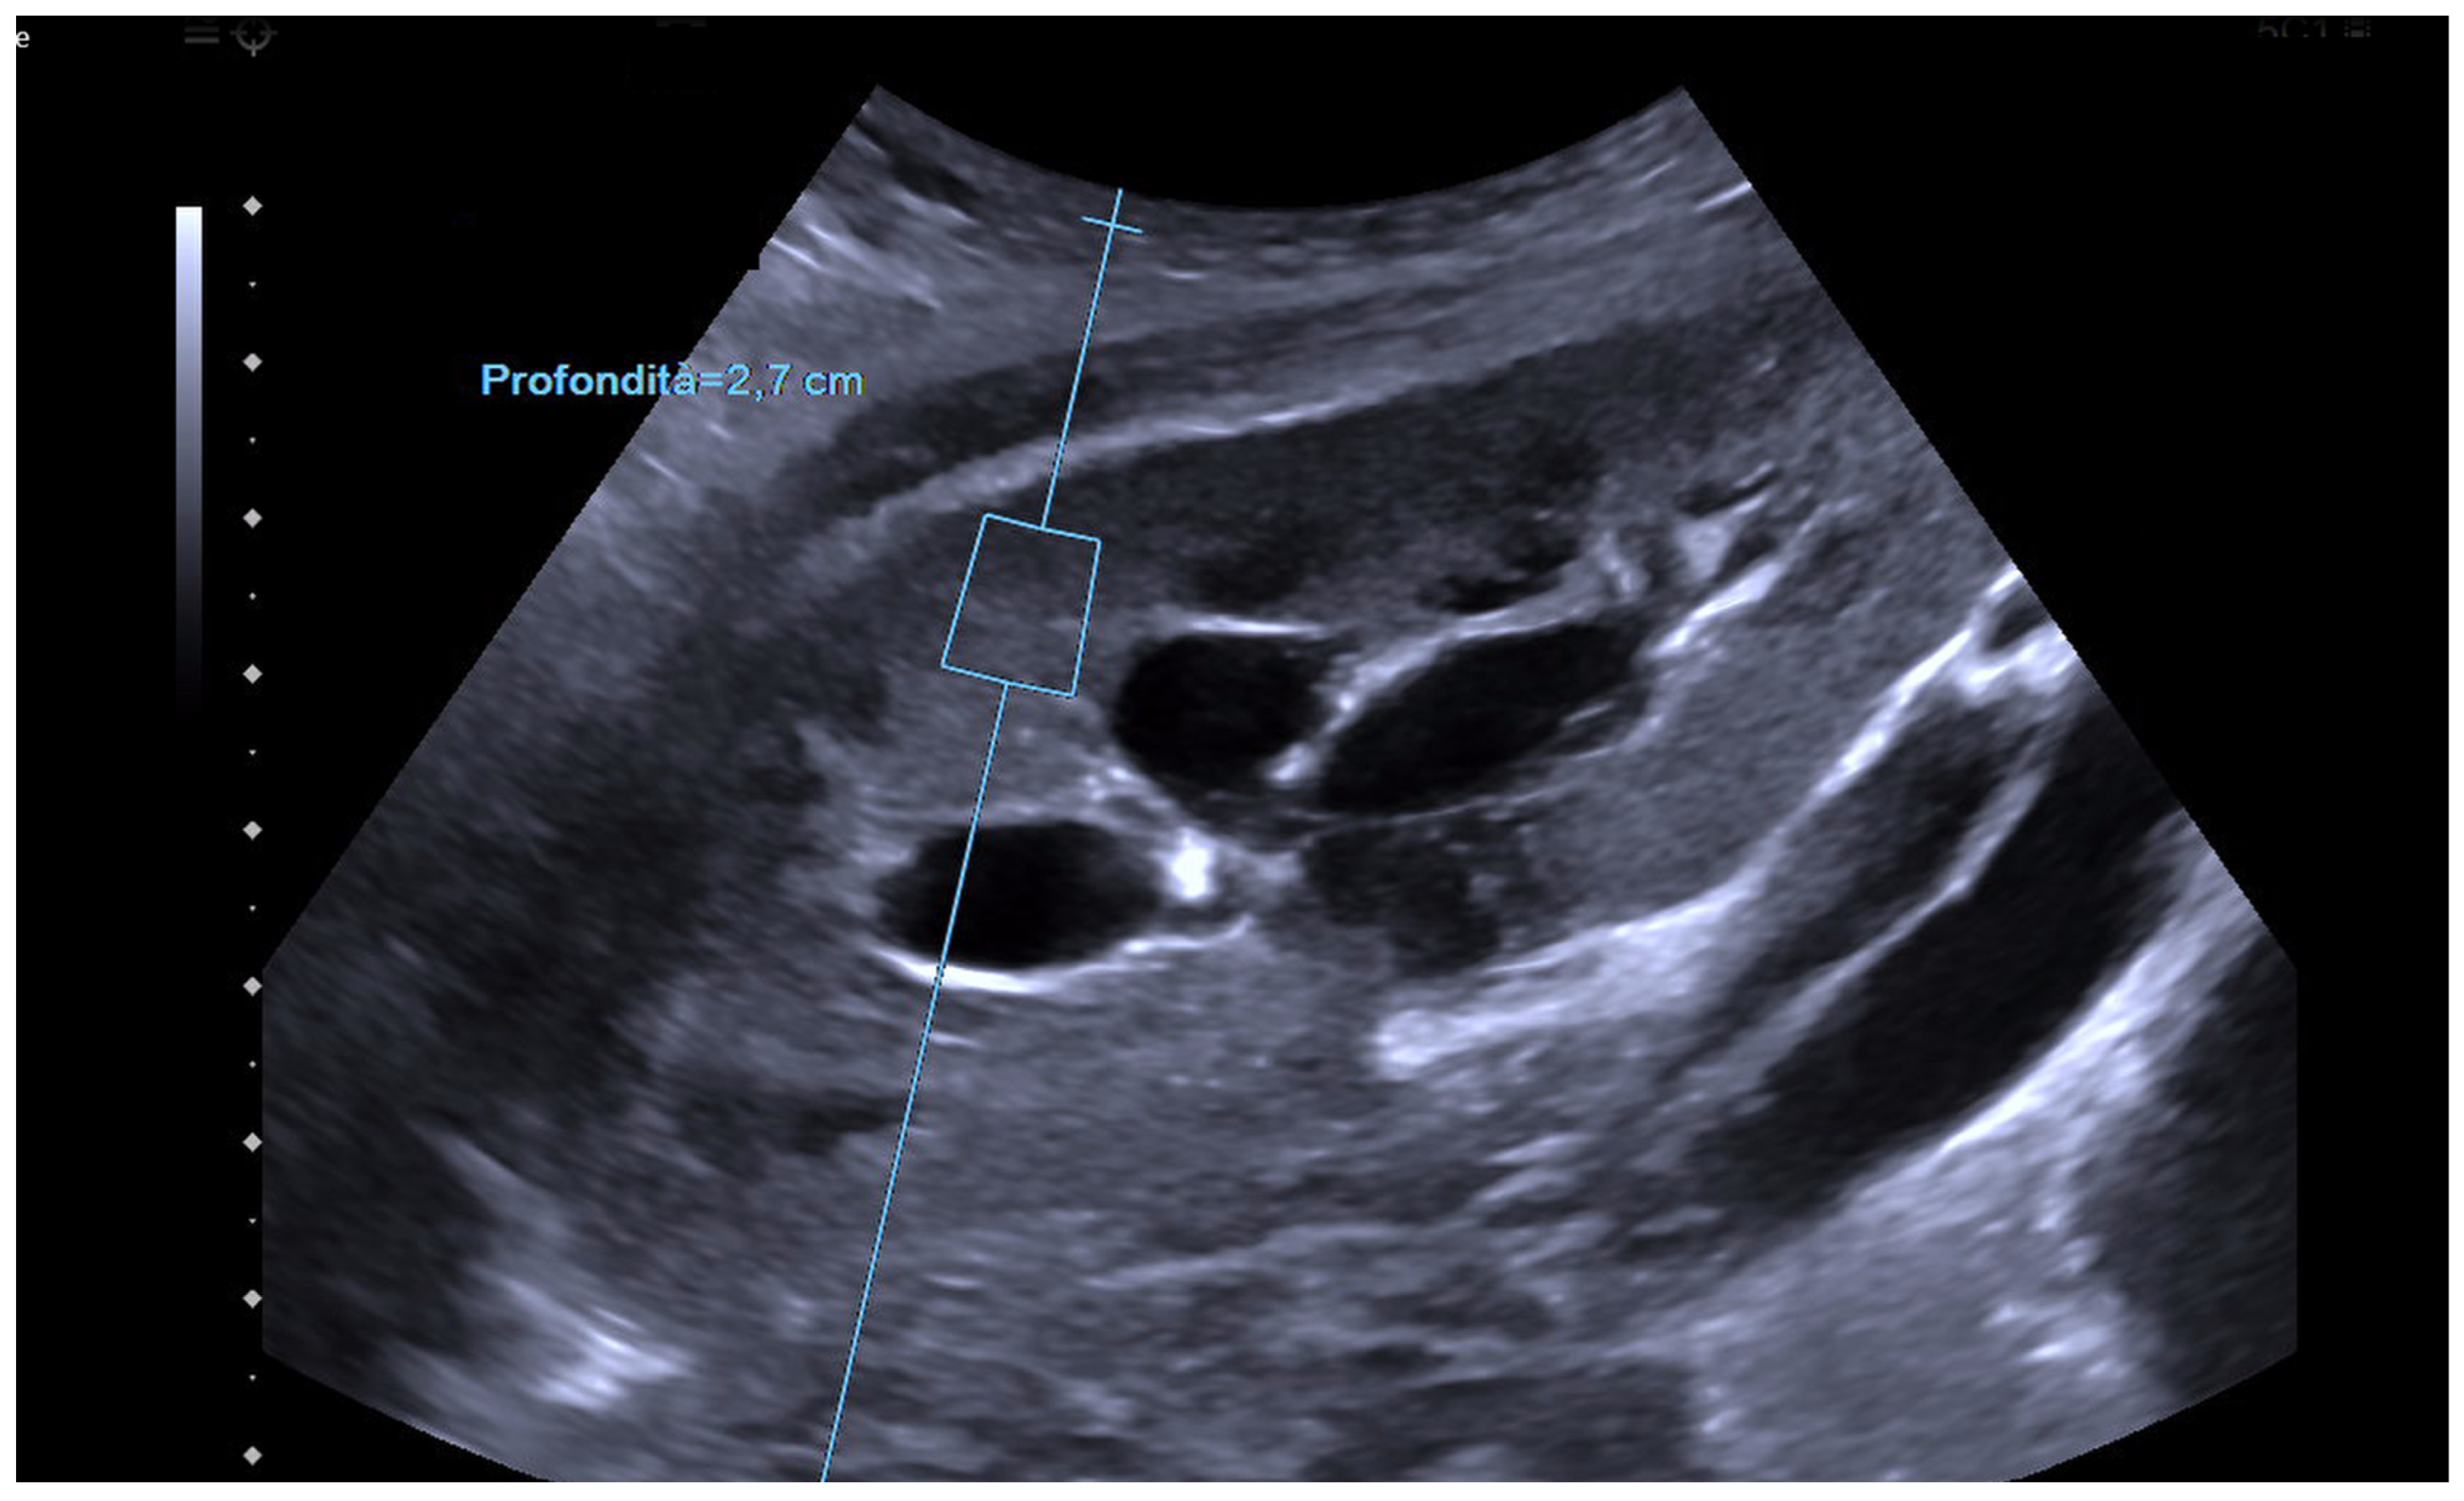

2. Principles of Operation and Comparison of Techniques

3. Elastography in the Kidney: Basic Technique and Limiting Factors